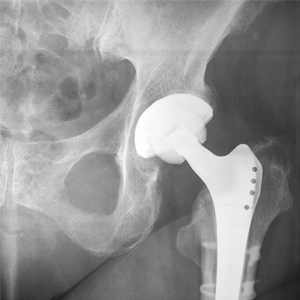

Total hip replacement is a surgical procedure in which the damaged cartilage and bone are removed from the hip joint and replaced with artificial components.

Hip replacement surgery is one of the most common orthopedic surgeries performed. It involves the replacement of the damaged hip bone (ball shaped upper end of the femur) with a ceramic ball attached to a metal stem that is fixed into the femur and placing a new cup with a special liner in the pelvis.

Revision hip replacement is a complex surgical procedure in which all or part of a previously implanted hip joint is replaced with a new artificial hip joint.

Primary hip replacement or hip arthroplasty is a surgical procedure in which the worn out or damaged parts of the hip joint are removed and replaced with artificial components called prostheses or implants that are made of metal, plastic, or ceramic.